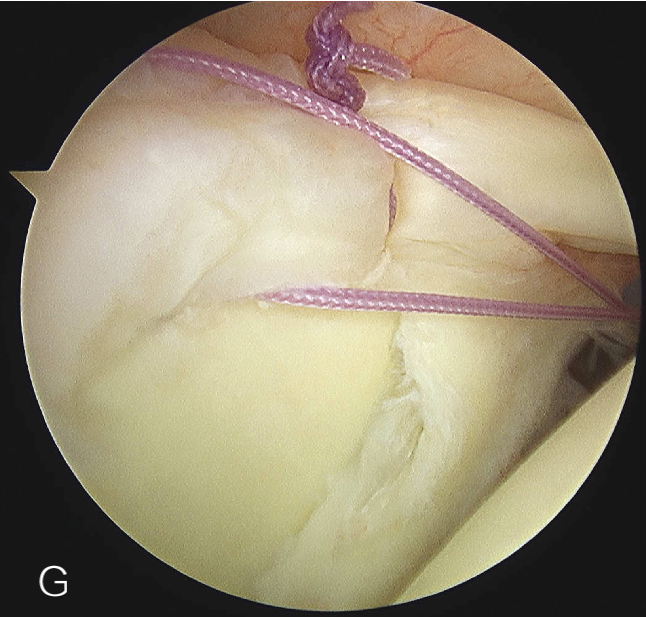

上盂唇修复

创建前方和后方入路时,与关节盂面成恰当角度,以便锚钉的置入。 高位和外侧放置前方入路可以有效地进行单纯上盂唇的修复。该入路位于肩袖间隙的高位和外侧,用腰椎穿刺针进行定位。非刚性套管有助于在肱二头肌腱附着部后方置入锚钉。 可用于 SLAP 修复的辅助入路包括 Wilmington 入路(肩峰后外侧角前方、外侧各 1 cm 处)或 Neviaser 入路(锁骨、肩峰、肩胛冈组成的三角形内,肩峰内侧 1 cm 处)。

B. 应首先用腰椎穿刺针确定辅助入路的恰当位置和方向。然后在皮肤上做一个小切 A B 口,钻头导向器置入关节。

修复处准备